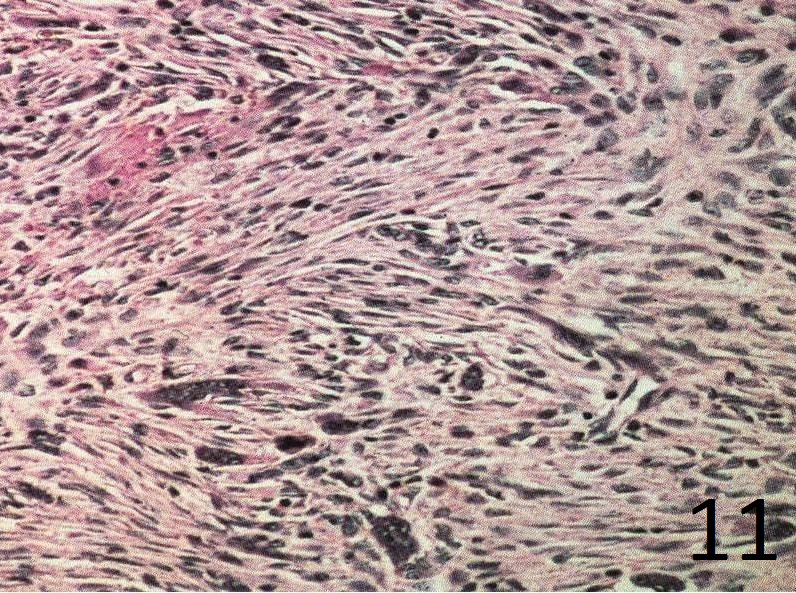

Microscopic

• Spindle cells are distributed in a storiform (swirling) pattern and mixed with other foci containing abundant histocytic cells (Fig. 10-11).

• Lipid laded histiocytes and macrophages

• Giant cells are present in irregular cluster

• Clusters of hemosiderin-iaden macrophages are dispersed

• The nuclei of the spindle cells and histocytes are regular

• Bland appearing cells with small uniform nuclei and no nuclear pleomorphism

Fig. 10

Fig. 11

Fig.11: High power view of the lesion shows the storiform patern, bland spindle cells, fibrous tissue and hemosiderin laden macrophages.